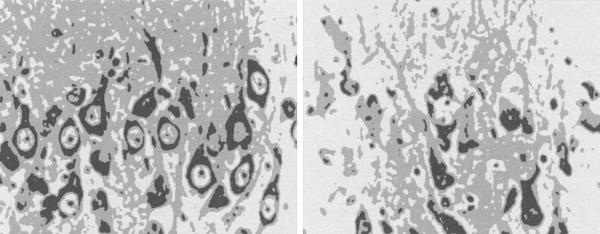

Ученые выдвинули предположение, что нервным клеткам гиппокампа, испытывающим постоянную большую нагрузку, в случае дополнительной нагрузки, например, из-за стресса, грозит отмирание. Получается, что стресс не только увеличивает риск получить высокое давление, инфаркт миокарда, язву желудка, проблемы с гормональной системой (нарушения роста и сексуальные расстройства), атрофию мышц (из-за расщепления белков для получения дополнительной энергии) и подавление иммунной системы (с увеличением числа инфекционных и раковых заболеваний); он также ведет к отмиранию нервных клеток в головном мозге, как наглядно демонстрирует рис. 1.9.

1.9. Нервные клетки в гиппокампе животного без признаков стресса (слева) и с явным их наличием (справа). Даже неспециалист четко распознает нормальные нервные клетки слева и «клеточный мусор», оставшийся после их отмирания, справа.